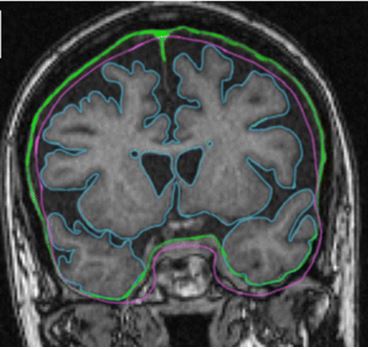

Estimated intracranial volume from FreeSurfer is biased by total brain volume

Since estimated intracranial volume (eTIV) from FreeSurfer is calculated from the alignment of the input MR images to the MNI305 brain atlas, and is not segmentation-based, a concern was raised that this might lead to a bias by total brain volume. This study managed to prove the existence of bias by total brain volume in eTIV.